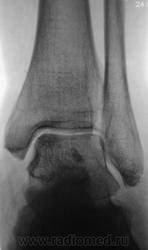

Трах... и вырос "грибок" на таранной...

Грибок этот не "трахогенной" природы. У меня вообще сомнения, что это вырост кости.

Понятно конечно, что "грибок" случайная находка. Но травма была...

Лодыжка срастется, никуда не денется. А вот оссифицирующий апоневрозит и данный то-ли экзостоз, то-ли оссификат капсулы будут периодически доставать и пациента, и врача-куратора.

Больше склоняюсь к хондромному телу, хоть в данном месте не встречал

Грибок этот не "трахогенной" природы. У меня вообще сомнения, что это вырост кости.  +1 !     Больше похоже на обызвествление сосудов . А хондроматоз - не подходит по локализации , хотя сама тень похожа внешне .